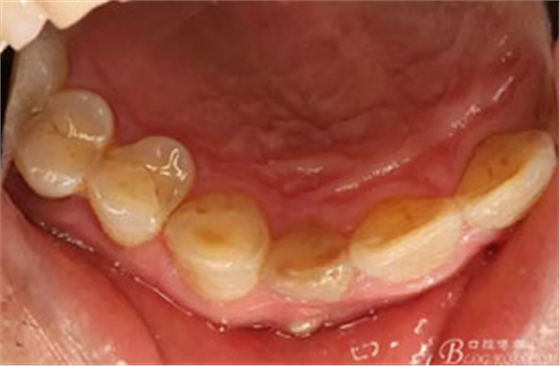

圖2. 12牙齒在我院進行熱牙膠根管充填+樹脂充填。

圖。一個月后患者復(fù)查: 唇側(cè)觀:11根尖區(qū)粘膜有一膿瘺,捫診溢膿,牙冠成灰褐色。根管治療無法治愈根尖病變,建議根管外科治療,患者同意手術(shù)。

圖3.腭側(cè)觀;11腭側(cè)牙齦正常,21腭側(cè)樹脂充填完好